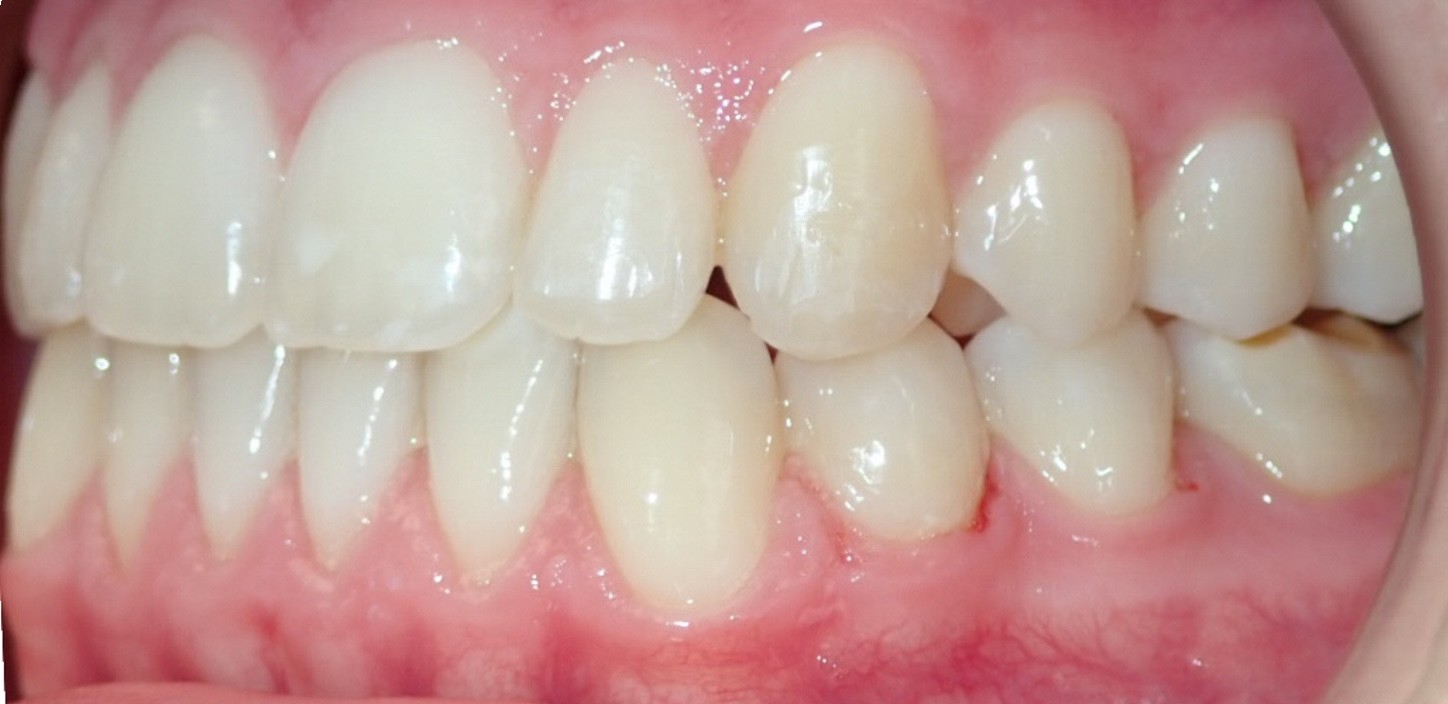

Final results

INTRAORAL